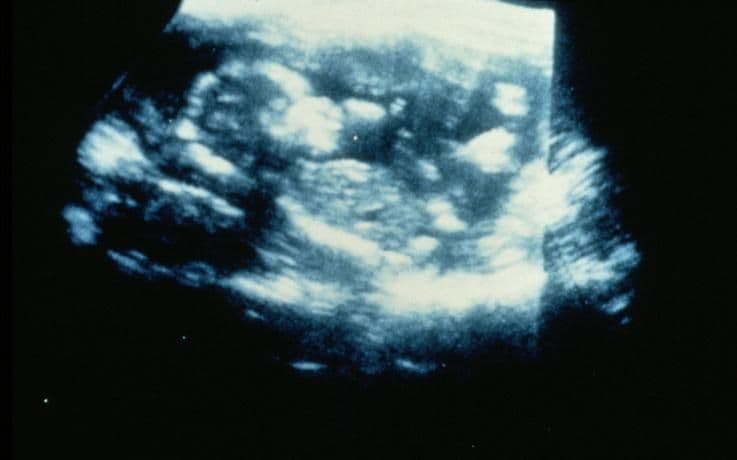

Shown here is a Doppler ultrasound scan. Your midwife may use a hand-held Doppler ultrasound machine to identify your baby’s heartbeat; Doppler scanning can also pick up sudden movements and the whoosh of blood through the placenta.